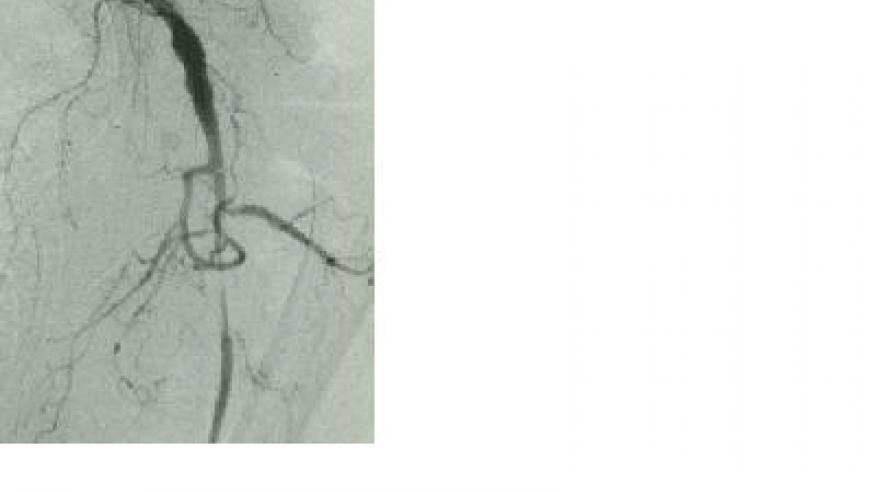

Giant cell arteritis (GCA) is a medium and large vasculitis, wherein only glucocorticoids (GC) treatment has been the mainstay of therapy. As many will require prolonged treatment, the hazards of GC are well known, lead to substantial toxicity and morbidity.